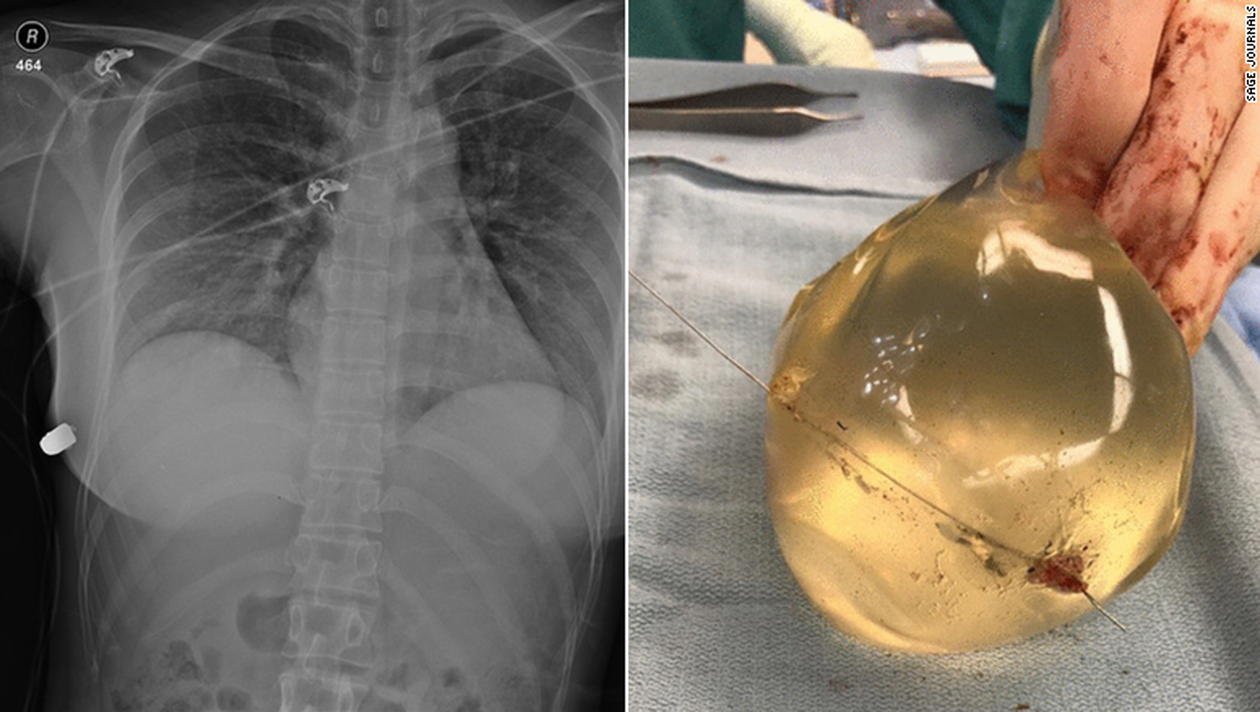

Într-un studiu de caz publicat în jurnalul medical SAGE săptămâna trecută, medicii au descris cum un implant mamar de silicon a ținut un glonț departe de organele vitale ale unei femei de 30 de ani.

Medicii au remarcat că implantul de silicon a fost probabil responsabil de devierea traiectoriei glonțului – salvând în cele din urmă viața femeii.

„Intrarea plăgii glonțului a fost pe sânul stâng, dar fractura coastei a fost pe partea dreaptă. Glonțul a intrat mai întâi în pielea din partea stângă, apoi a ricoșat peste stern în sânul drept și i-a rupt coasta în partea dreaptă.”, a explicat medicul.

„Implantul a provocat schimbarea traiectului glonțului”, a spus el.

Femeia a suferit o rană prin împușcare, coaste rupte și implanturi rupte.

„Pe partea stângă se află inima și plămânii – dacă glonțul ar fi intrat în piept, ar fi avut o vătămare mult mai gravă, care poate pune viața în pericol”, a adăugat McEvenue.

Medicii au găsit un obiect dur, asemănător glonțului în peretele toracic anterior inferior al femeii sub pieptul drept.

Folosind radiografii traumatice, medicii au reușit să detecteze glonțul în peretele toracic lateral drept, o coastă fracturată și bule de aer în sânul stâng. Medicii au cloncluzionat că glonțul ”a călătorit” de la sânul stâng la peretele toracic drept.